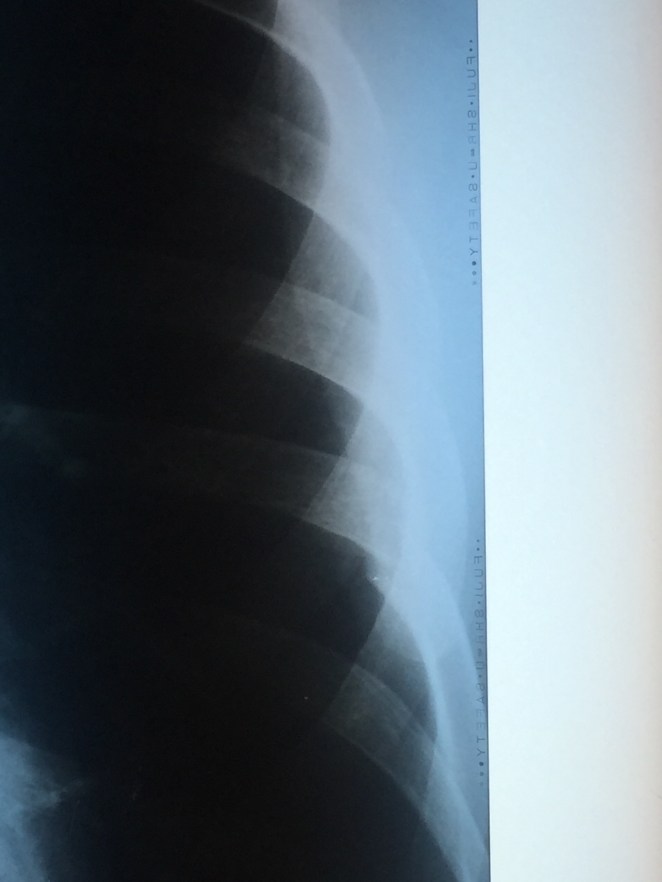

Made it to Lukla earlier today and headed straight to the hospital where an X-ray confirmed I have fractured my L7 rib from coughing these last few weeks.